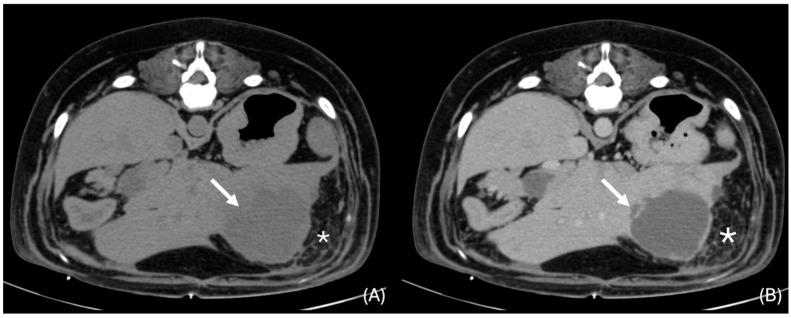

Bacterial liver parenchymal infections in dogs are rarely documented, and their imaging characteristics are scarce in the veterinary literature, especially in Computed Tomography (CT). This retrospective multicentric study aimed to describe the CT characteristics of parenchymal bacterial liver infection and abscessation in dogs and compare them with the human literature. Twenty dogs met the inclusion criteria. All dogs, except one, showed discrete hepatic lesions consistent with pyogenic liver abscess (19/20). A single case showed diffuse liver changes, which was diagnosed with granulomatous bacterial hepatitis (1/20). Multifocal lesions were associated with the presence of abdominal pain ( = 0.023). CT characteristics of pyogenic liver abscesses in our study resemble those described in the human literature, with multifocal (14/19) or single (5/19), round or ovoid (19/19), hypoattenuating hepatic lesions, which are better visualised in post-contrast images. Pyogenic liver abscesses can also show features such as the "cluster sign" (8/19), transient arterial segmental enhancement (6/10), rim enhancement (6/19), and intralesional gas (4/19). Additional CT findings, such as local lymphadenomegaly (18/20), peritoneal fat stranding (14/20), and peritoneal fluid (13/20), are also commonly observed.

犬细菌性肝实质感染鲜有文献记载,其影像学特征在兽医文献中也很罕见,尤其是在计算机断层扫描(CT)方面。这项回顾性多中心研究旨在描述犬肝实质细菌感染和脓肿形成的CT特征,并与人类文献进行比较。20只犬符合纳入标准。除1只犬外,所有犬均表现出与化脓性肝脓肿相符的离散性肝脏病变(19/20)。1例犬表现为弥漫性肝脏改变,诊断为肉芽肿性细菌性肝炎(1/20)。多灶性病变与腹痛有关( = 0.023)。我们研究中化脓性肝脓肿的CT特征与人类文献中描述的相似,表现为多灶性(14/19)或单灶性(5/19)、圆形或椭圆形(19/19)、肝脏低密度病变,在增强后图像中显示更佳。化脓性肝脓肿还可表现出“簇状征”(8/19)、短暂性动脉节段性强化(6/10)、边缘强化(6/19)和病灶内气体(4/19)等特征。其他CT表现,如局部淋巴结肿大(18/20)、腹膜脂肪条索征(14/20)和腹腔积液(13/20)也较为常见。